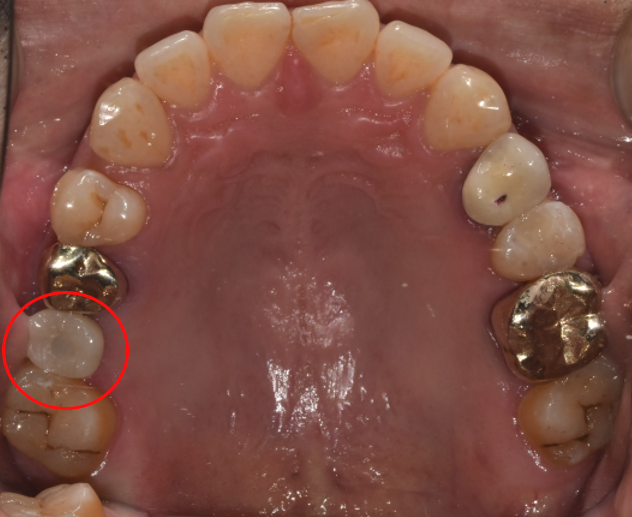

청담역치과 2021-11-01

4단계는 자연치아와 흡사하게 본을 떠서 만든 인공치아를 장착해 치료를 완료했습니다.

임플란트 치료 전&후

(좌)2021-07-22 / (우) 2021-11-01

임플란트 치료 BEFORE & AFTER입니다. 비어있는 공간에 치아가 알맞게 식립된 것을 알 수 있습니다.